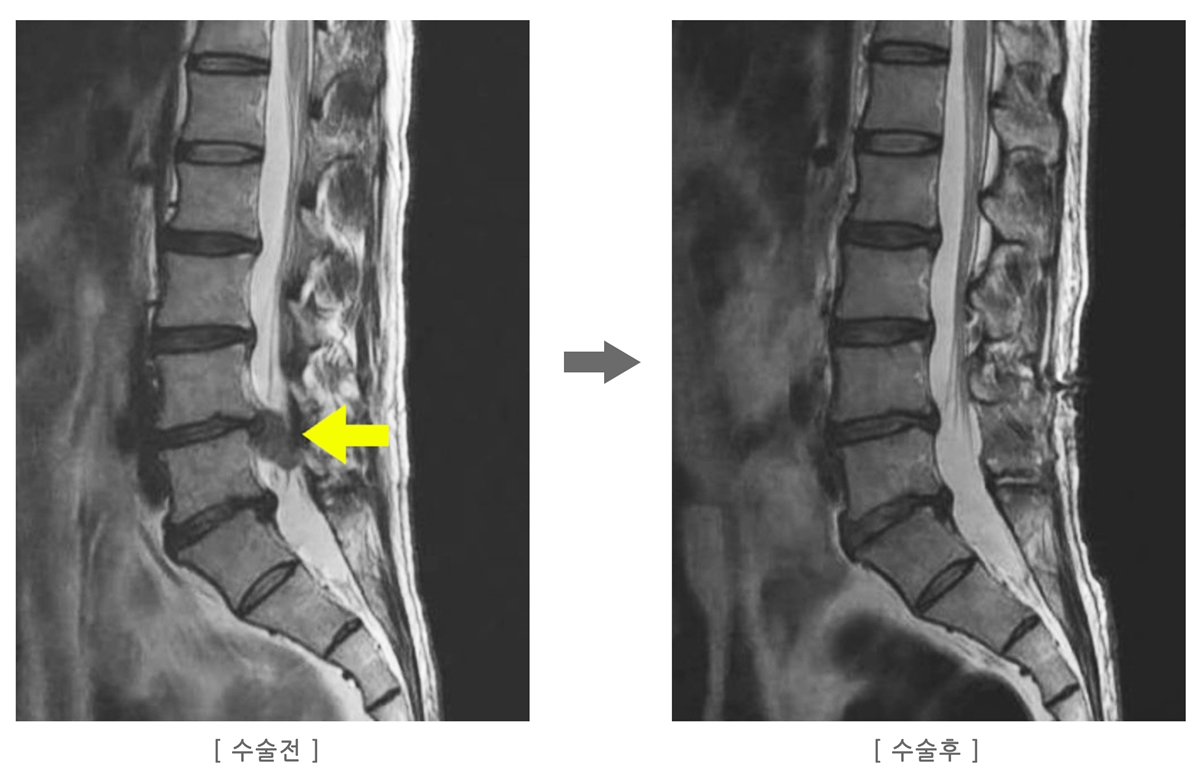

A. 4주 이상 지속되는 통증, 3단계 이상의 방사통, 근력 저하·감각 저하가 느껴진다면 MRI를 통해 정확한 상태를 확인하는 것이 좋습니다.